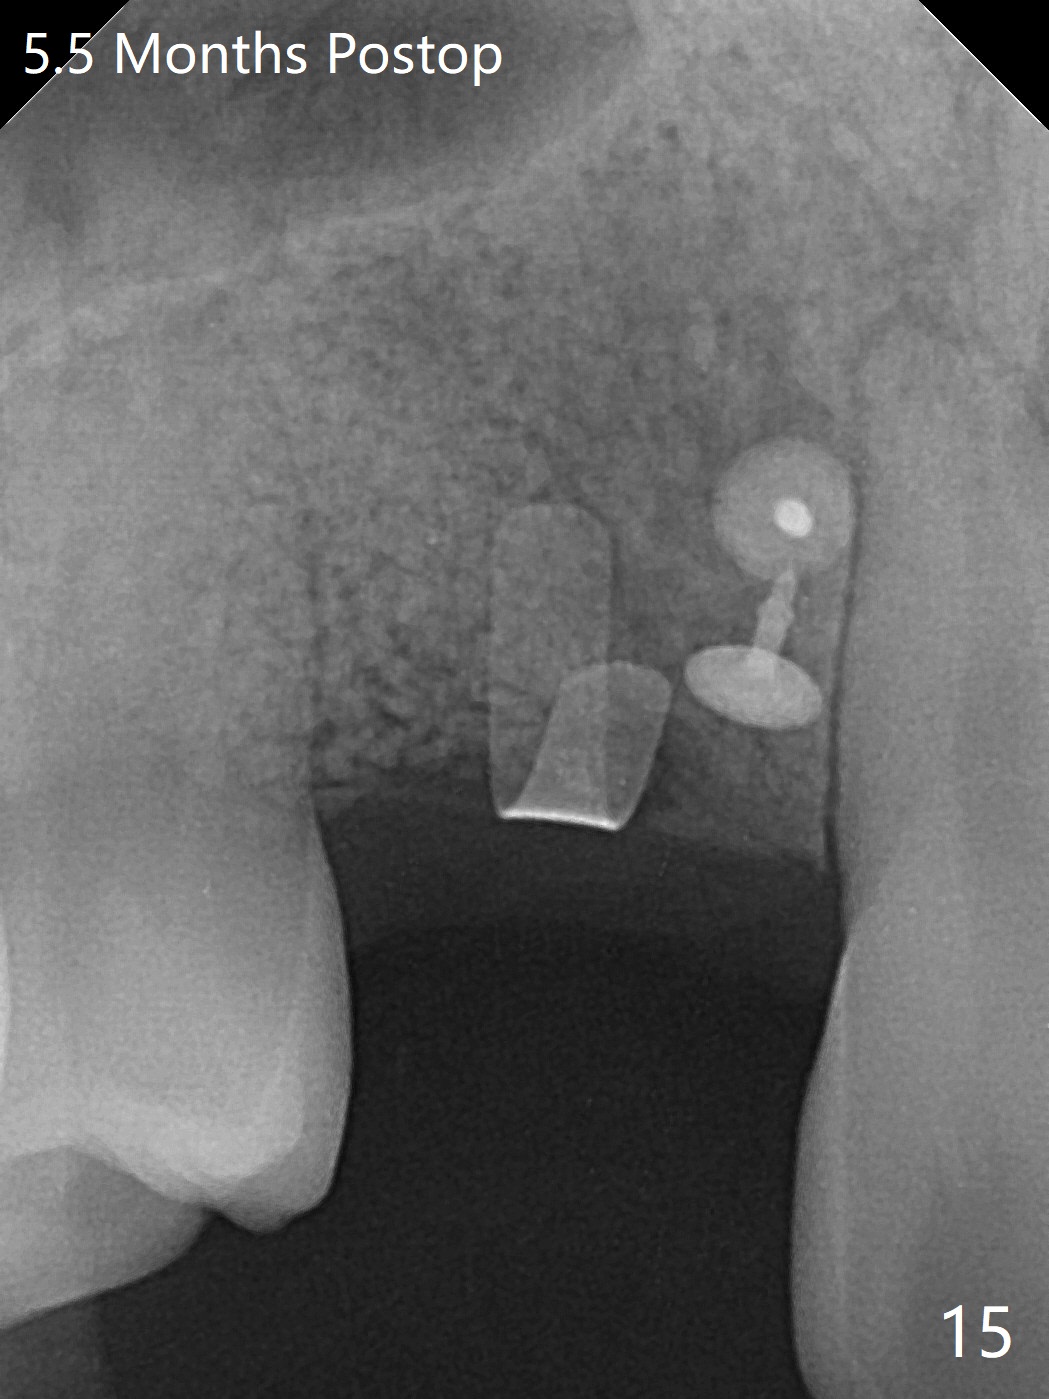

18岁男从外州大学回来,无症状,但是6号牙(右上尖牙)颊侧瘘道(图一,二(角化龈充分(箭头))),根尖片显示植体近中骨吸收(图三:*),而对侧植体仿佛骨整合(图四)。患侧切开后发现植体颊侧暴露,松动。拔除后骨缺损由粘性骨粉修复(图七,九:*),覆盖PRF膜(图七:P)和带钛网(图九:^)不可吸收膜(图五-七),后者用两个小钉子固定(图六(腭侧),七(颊侧),九),使用新的刀片和一个特殊尖头剥离器在颊侧骨膜下相当广泛分离,使用PTFE缝线,粘膜下水平褥式缝合之后(图八:箭头),多个垂直间断缝合,两个乳头垂直褥式缝合。术后一周伤口没有裂开,术后疼痛肿胀已经消退(图十)。术后十八天牙槽嵴仿佛比对侧还要宽(图十一,三与图十二,四(取模)对比)。术后5.5个月伤口没有裂开,牙槽骨,角化龈宽(图十六),与钛网和两个小钉子固定有关(图十五,十七)。CT显示牙槽骨只能容纳2.5或者3.0毫米植体(图十八)。11号牙植体牙冠粘固后没有骨质吸收(图十九),其实10,11号牙颊侧骨板隆起(图二十至二十二),而6植体失败,颊侧骨板吸收,甚至累及5号牙(图十七)。